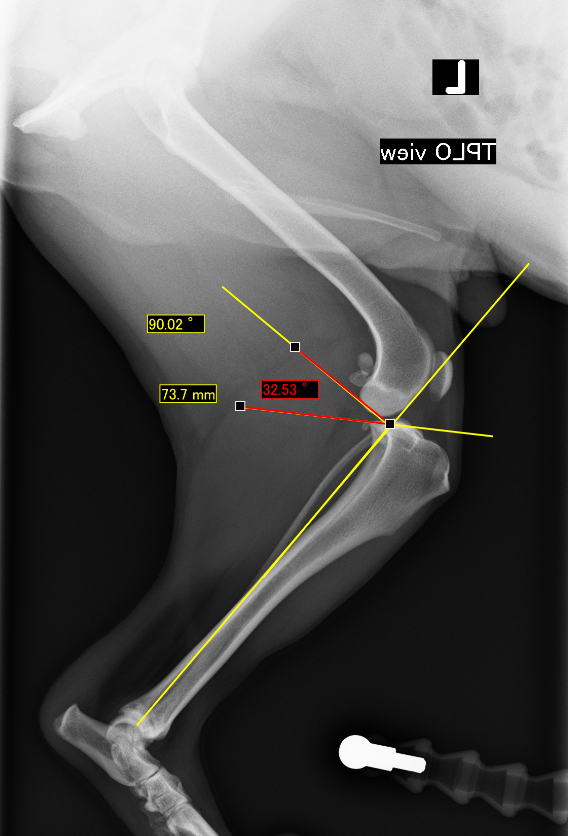

膝蓋骨内方脱臼(前十字靭帯断裂併発)